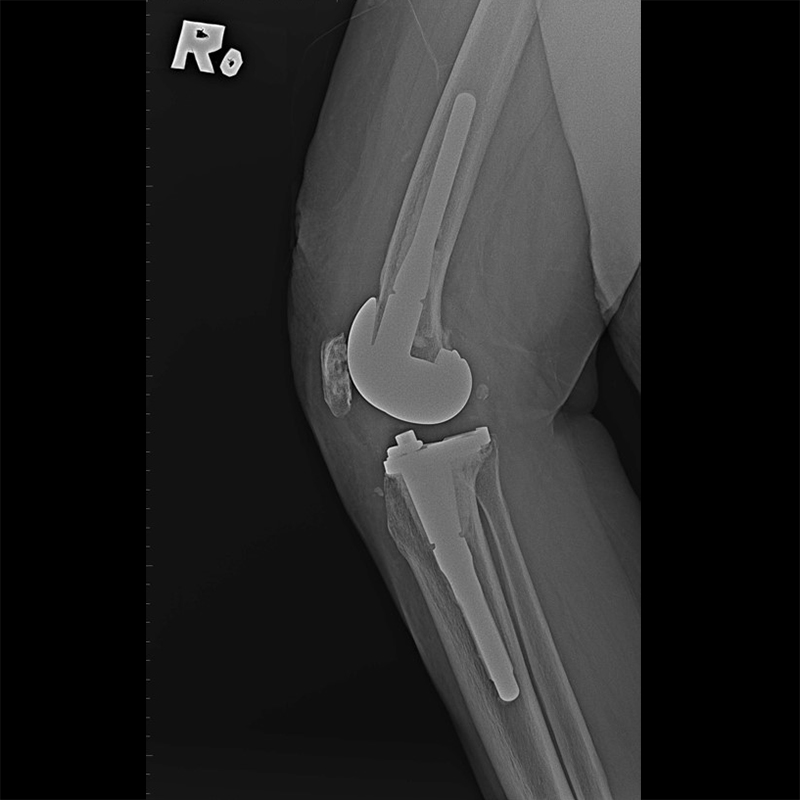

外院失敗本院再置換 首頁 案例分享 膝關節手術 外院失敗本院再置換 蕭女士 69歲 術前 術後 81歲 林女士 術前 術後 蕭女士 69歲 術前 術後 鄒女士 69歲 術前 術後 李女士 74歲 術前 術後 吳女士 71歲 術前 術後 謝女士 65歲 術前 術後